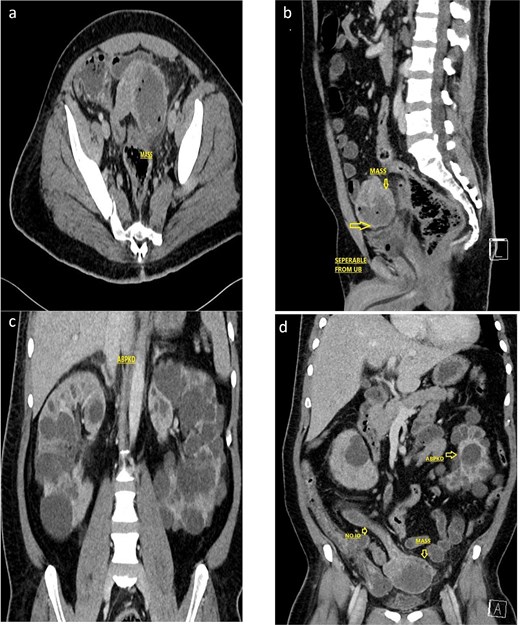

Following hemodynamic stabilization, and improvement in lactate levels, further imaging was pursued to identify the source of hemoperitoneum and guide surgical management. Despite underlying renal dysfunction, a contrast-enhanced computed tomography (CT) was performed after multidisciplinary discussion with the nephrology team, as the potential diagnostic benefit was considered to outweigh the risk of contrast exposure. Renal protective measures were implemented, including optimization of intravascular volume and avoidance of nephrotoxic agents. Contrast-enhanced CT demonstrated a 7.0 × 8.6 × 7.7 cm exophytic jejunal mass with central necrosis, peripheral enhancement, mesenteric fat stranding, and minimal free intraperitoneal fluid, without pneumoperitoneum (Fig. 2). Radiologic features suggestive of malignant GIST included tumor size >5 cm, exophytic growth, and central necrosis [9].

Contrast enhanced CT scan of the abdomen and pelvis (a, axial; b, sagittal) showed a 7.0 × 8.6 × 7.7 cm, exophytic mass having cystic and soft tissue components, a central hypodense area with air foci within, arising from the Jejunal loop, with mesenteric fat stranding and suspected intramural invasion. Associated findings included pericholecystic fluid, sub-centimetric mesenteric lymphadenopathy, subtle mesenteric fatty strandings, and bilateral renal cysts. Not associated with any intestinal obstruction or any obvious mesenteric tethering. The lesion is identified separable from the urinary bladder. (c, d) Coronal CT imaging showing the polycystic kidney disease.